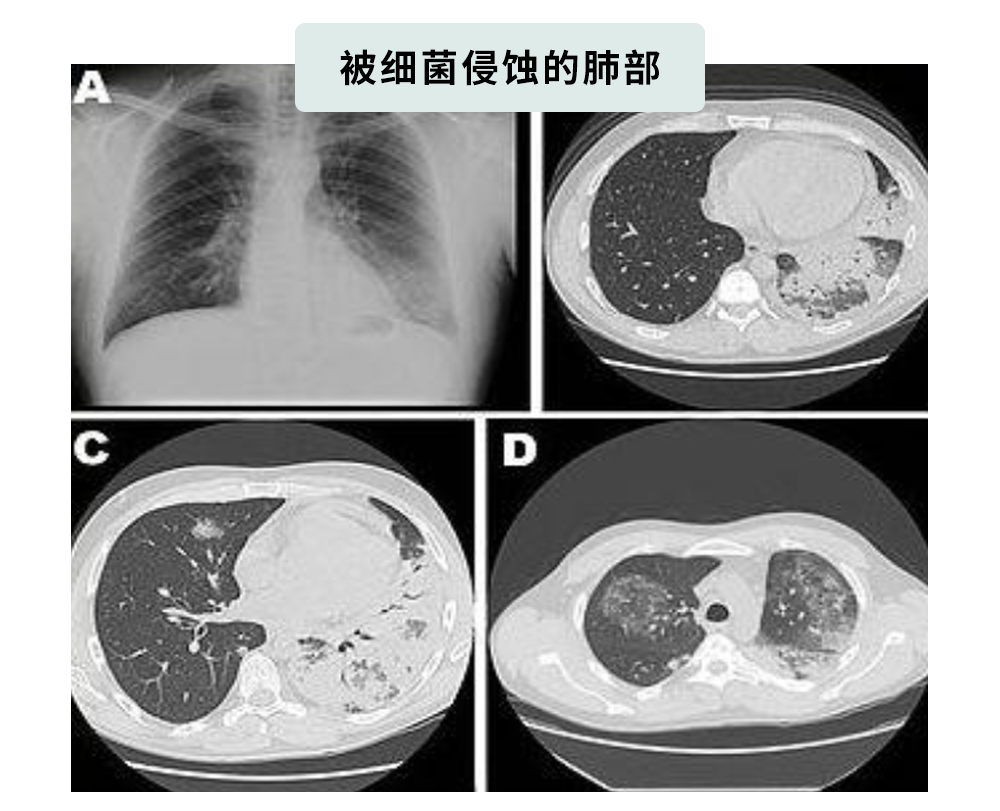

一旦吸入军团菌,就有可能感染“军团菌肺炎”,引起急性呼吸衰竭。

不好好治疗的话,这玩意儿致死率能高达30%!

开头那个不幸住进ICU的老哥,就是被“军团菌”害的。